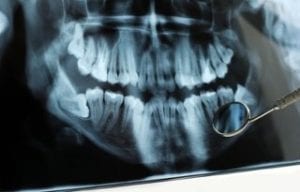

Wisdom Teeth Removal: What Parents Need to Know

Wisdom teeth removal, dental professionals will tell you, is necessary in most people, since these third molars become problematic more often than not. Most often, the problem is that there isn’t enough room in the mouth for wisdom teeth to emerge properly, which can lead to a variety problems, including impactions, infections and damage or shifting in adjacent teeth. If your kids have reached high......

Have you been told that your child needs wisdom teeth extraction? Oral surgeon Dr. Robert Emery advises that wisdom teeth that will be problematic – which can often be determined before these teeth emerge – should be removed as early as possible. While many parents have been given that advice, the reasons early removal is best aren’t always explained in detail. Here are three important......